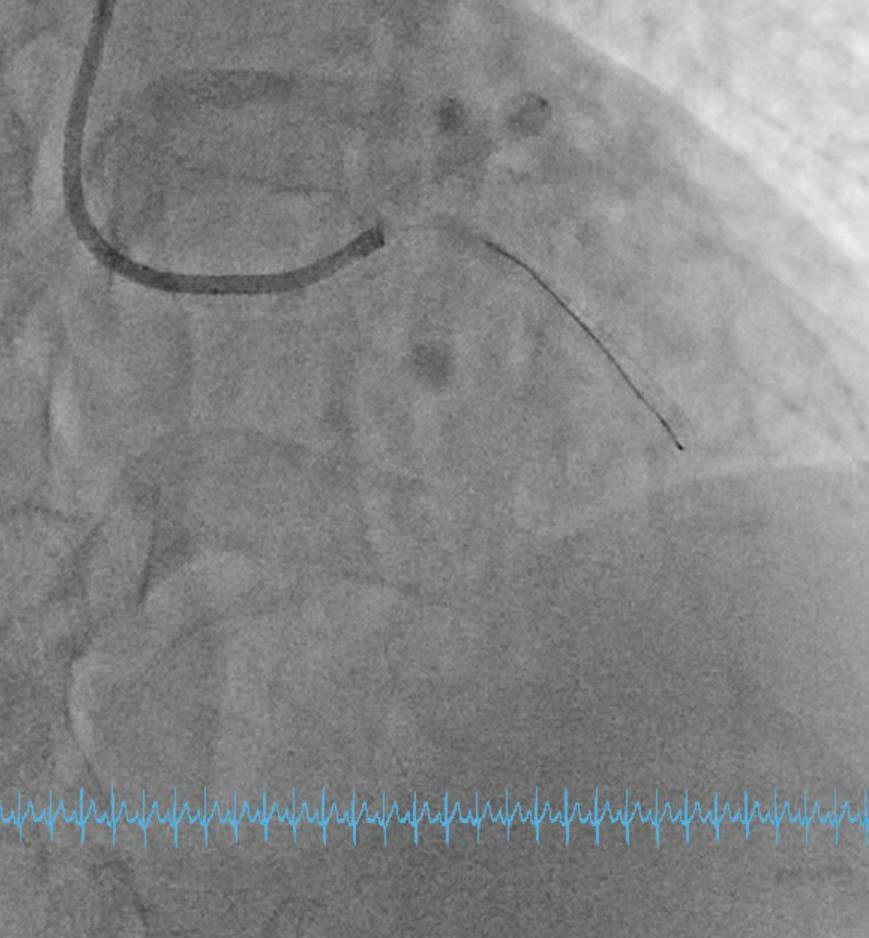

Engage the guiding catheter into the LCX ostium and advance a wire for anchoring in the LCX. After withdrawing the guiding catheter from the ostium and performing coronary angiography, it was observed that the LAD ostium originated separately from the LCX ostium and was located lower in the RAO–CRA view.Multiple attempts to selectively wire the LAD ostium using a 6 F SPB 3.0 guiding catheter (Asahi, Japan) from outside the LAD ostium were unsuccessful. The guiding catheter was then exchanged for a 6 F JL 3.5, and a Sion Blue wire was successfully advanced through the LAD ostium into the distal segment.DSA and IVUS post-intervention showed minimal stent area of 8.83 mm2, reached 112 % of distal reference vessel diameter. Stent covered LAD ostium with an area of 9.64 mm2 and was 2 mm inside the aortic artery. There was no protrusion, no dissection.